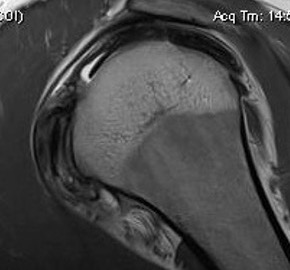

MRI

LTLT